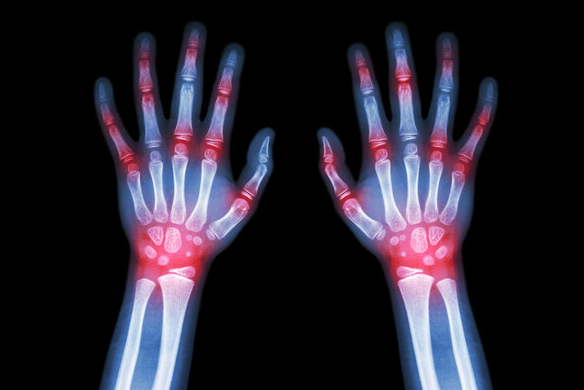

类风湿关节炎患者因自身疾病的发病特征,常常存在着手腕部关节疼痛和晨僵的困扰,而这些困扰也影响着患者的日常生活。因此搜集了一些拉筋伸展的小妙招,通过这些简单的手部运动能够帮助患者缓减疼痛和缩短晨...[详细]

类风湿病常见的症状是什么样的? 郑州类风湿专科医院 介绍,类风湿病在生活中还是比较常见的,它给患者的身体有很大的危害性,给患者的生活造成很大的影响,因此在日常如果发现该病的症状时还需尽早到正规医...[详细]